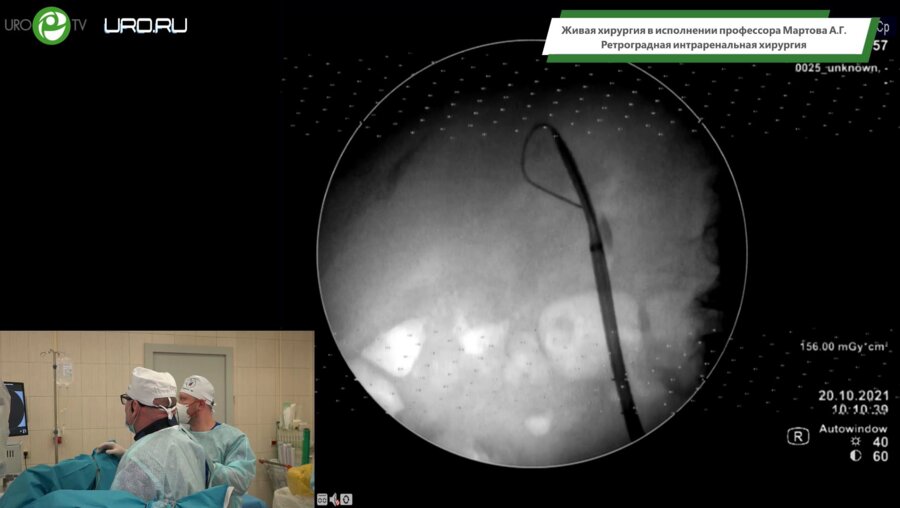

Мартов Алексей Георгиевич

Доктор медицинских наук, профессор, член-корреспондент Российской Академии Наук.

Президент Российского общества по Эндоурологии и Новым Технологиям.

Заместитель председателя Российского Общества Урологов.

Заведующий кафедрой урологии и андрологии МБУ ИНО ФГБУ ГНЦ ФМБЦ им. А.И. Бурназяна ФМБА России, ведущий научный сотрудник отдела урологии и андрологии МНОЦ МГУ им. М.В. Ломоносова, директор урологического центра ФБУ "ЦКБ Гражданской Авиации".